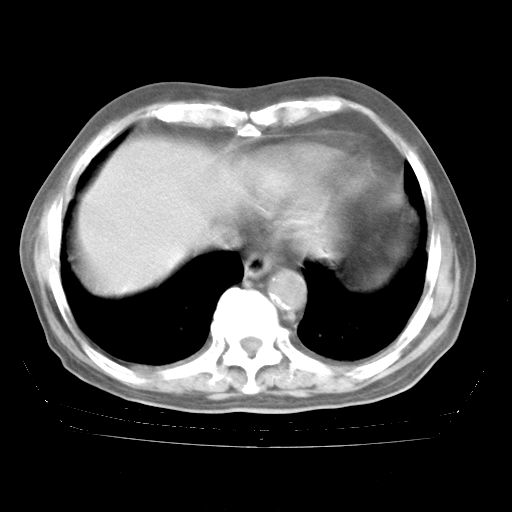

4月28日肺部CT——再次出现类似去年5月9日——透光度降低,“间质性”改变。

4月28日肺部CT